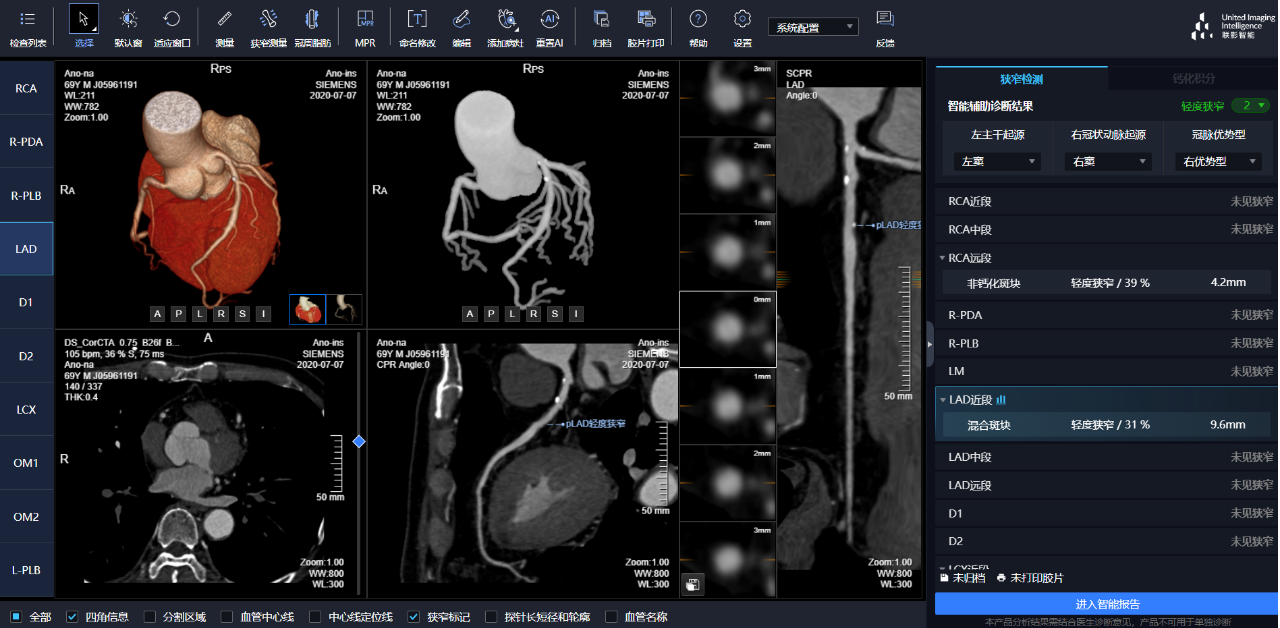

相較于傳統(tǒng)人工閱片,在聯(lián)影智能AI軟件的輔助下,640CT閱片的靈敏度和閱片效率均有顯著提升,對(duì)于細(xì)微骨折乃至于隱匿性骨折的判斷,準(zhǔn)確度更高,極大地減少了漏診及誤診。

通過3D視圖可任意旋轉(zhuǎn)觀看血管全貌,AI秒級(jí)實(shí)時(shí)計(jì)算重建血管,可實(shí)現(xiàn)多維輔診包含:板塊定性定量分析、狹窄評(píng)估、心肌橋檢出、支架檢出、鈣化積分,全程AI關(guān)注心血管健康。